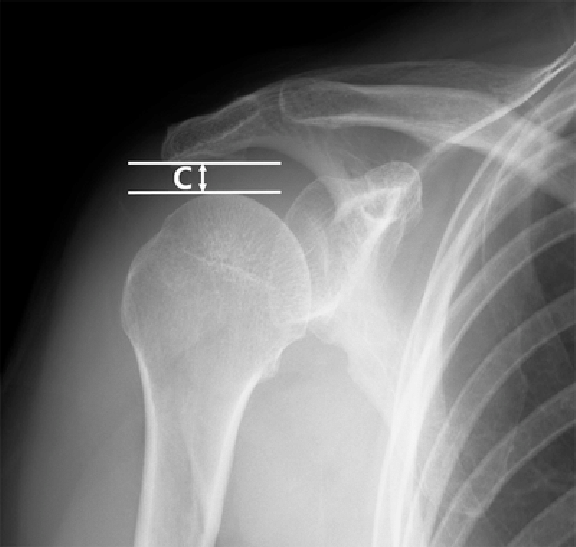

ㄱ. 봉우리위팔거리(AHD)

- 봉우리 밑면과 몸 쪽 위팔뼈 사이의 거리

- 20도 벌림 시 : 위팔뼈머리가 봉우리 밑면에 가장 가까이 위치(7.5mm)

- 85도 벌림 시 : 가시위근 먼쪽 부착부위가 봉우리 밑면에 가장 가까이 위치(2.6mm)

- 150도 벌림 시 : 몸 쪽 위팔뼈몸통이 봉우리 밑면에 가장 가까이 위치(5mm)

- 벌림 시 봉우리밑 공간 높이가 너무 좁으면 봉우리밑 공간에 있는 구조가 끼여 통증 발생